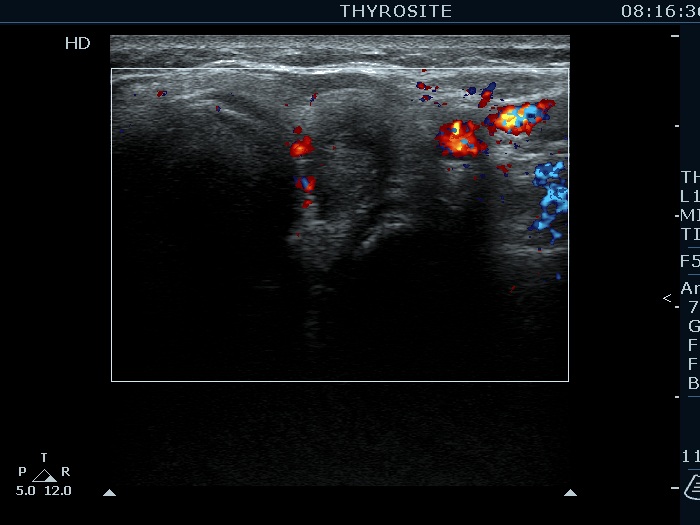

Granulation around surgical thread (cytological diagnosis) - case 1423

There is a relatively large echonormal tissue in the central part of the hypoechogenic mass. Note the acoustic shadowing. The lesion is avascular.